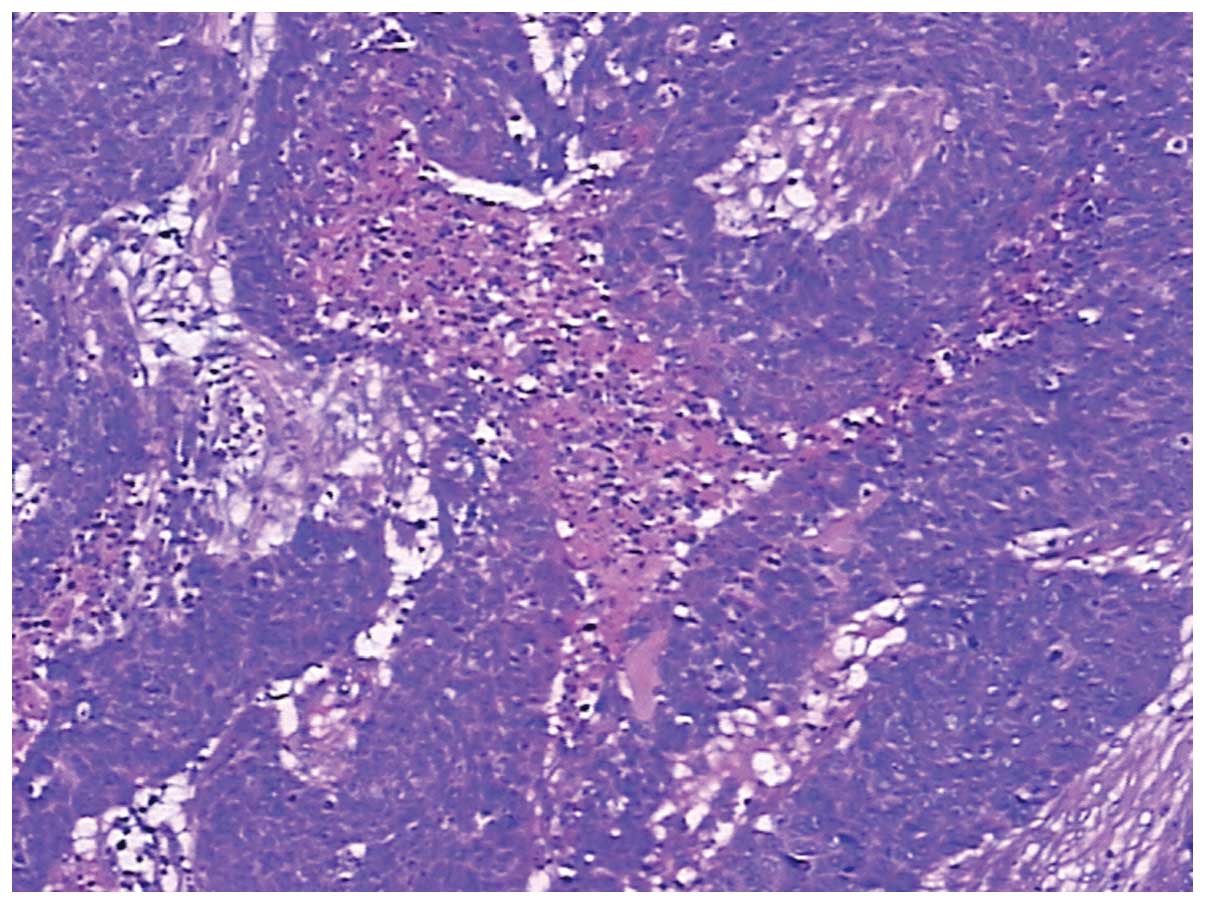

Laboratory studies revealed that the complete blood count and blood chemistry were within the normal range. No abnormal tumor markers were detected: Cancer antigen (CA)125, 3.15 KU/l (<35.00 KU/l); CA15-3, 2.16 KU/l (<35.00 KU/l); CA19-9, 3.57 KU/l (<35.00 KU/l); CA242, 2.58 KU/l (<20.00 KU/l); α-fetoprotein, 6.57 ng/ml (<20.00 ng/ml); carcinoembryonic antigen, 2.25 ng/ml (<5.00 ng/ml); neuron-specific enolase, <1.0 ng/ml (<13.00 ng/ml); ferritin, 19.70 ng/ml (male, <322.00 ng/ml; female, <219.00 ng/ml); human growth hormone, 2.20 ng/ml (<7.50 ng/ml); or β-human chorionic gonadotropin, <0.03 mIU/ml (<3.00 mIU/ml). Axial positron emission tomography (PET), computed tomography (CT), PET/CT and maximum intensity projection images are shown in Fig. 1. PET/CT identified a hypermetabolic lesion in the interspace between the liver and stomach. There was no additional fludeoxyglucose (18F) uptake, which indicated a primary site on the transaxial PET/CT scans of the head, neck, chest, pelvis, extremities or other abdominal organs (including the spleen, pancreas, gallbladder, kidney, large and small intestines). The patient subsequently underwent surgical resection. The tumor was located in the interspace between the liver and stomach, it measured 6×5 cm, was close to the left gastric artery, and invaded the gastric wall and the pancreas. Intraoperative fast pathological sections revealed that the tumor tissues were composed of nidulant, multi-mitotic cells and necrosis, which were identified as SCC (Fig. 2); therefore, the tumor was resected and a proximal gastrectomy was performed.

Figure 1

Positron emission tomography-computed tomography demonstrated a hypermetabolic lesion (standardized uptake value, 12.8) in the interspace between the liver and stomach. There was no additional fludeoxyglucose (18F) uptake, which indicated a primary site in other organs.

Figure 2

Intraoperative fast pathological sections revealed that the tumor tissues were composed of nidulant, multi-mitotic cells and necrosis, which was reported as a squamous cell carcinoma. (Hematoxylin and eosin staining; magnification, ×100).